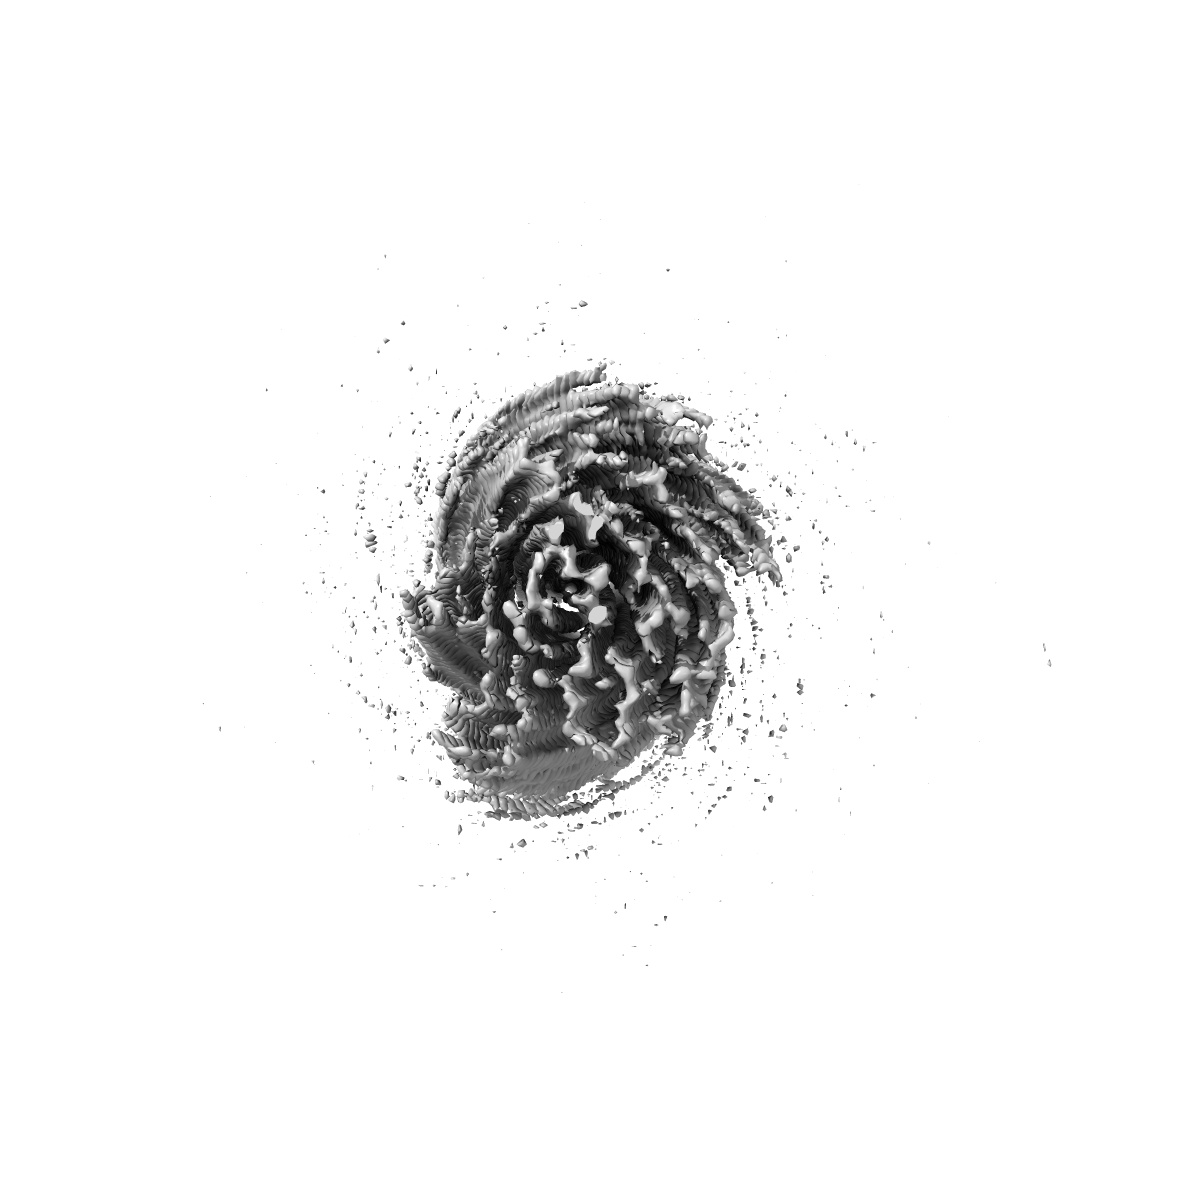

Structure of heteromeric amyloid filament of TDP-43 and AXNA11 from FTLD-TDP Type C (variant 2)

Helical reconstruction2.9 Å

Sample: heteromeric amyloid filament of TDP-43 and AXNA11 from FTLD-TDP Type C (variant 1)

Heteromeric amyloid filaments of ANXA11 and TDP-43 in FTLD-TDP Type C.

- Arseni D, Nonaka T, Jacobsen MH, Murzin AG, Cracco L, Peak-Chew SY, Garringer HJ, Kawakami I, Suzuki H, Onaya M, Saito Y, Murayama S, Geula C, Vidal R, Newell KL, Mesulam M, Ghetti B, Hasegawa M & Ryskeldi-Falcon B. (2024) Heteromeric amyloid filaments of ANXA11 and TDP-43 in FTLD-TDP Type C. Nature,